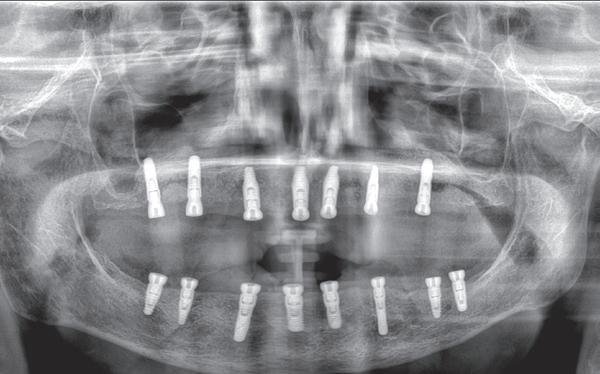

Op basis van de eerste indruk die ik krijg tijdens het globale klinische onderzoek, wordt een orthopantamogram (zie OPT bij intake) gemaakt. Samen met de meegestuurde röntgenopnames (zie solo’s) wordt eenvoudig vastgesteld dat er sprake is van ernstig botverlies, bijvoorbeeld bij de 16, 17 en de 18 tot 100% verlies aan alveolair bot. De 16 vertoont daarnaast een grote peri-apicale laesie. In het eerste kwadrant lijkt daarom alleen de 12 een goede prognose te hebben. De 12 vormt samen met de 16 een vierdelige brug en deze constructie lijkt dus verloren. Overigens vermoed ik dat de 12 eigenlijk een cuspidaat is en ontbreekt de 12 (agenesie). Daarnaast worden sterk verdiepte ontstoken pockets geconstateerd bij de 16, 17 tot 12 mm en zijn de elementen sterk verhoogd mobiel. De 11 lijkt als enige element van de gehele dentitie niet te zijn behandeld.

Dit betekent in eerste instantie dat de dentitie invasief wordt gesaneerd wat neerkomt op totaal extractie: een volledige gebitsprothese voor in de boven- en onderkaak. Een implantaat gedragen vaste voorziening kan op termijn aan de wens van de patiënt voldoen. De chirurgische behandeling omhelst het plaatsen van implantaten op geleide van een boormal eventueel in combinatie dan wel separaat uit te voeren botopbouw en bilaterale sinuslift. Zes maanden na de eerste fase wordt het mogelijk de tweede fase uit te voeren, namelijk de abutment chirurgie. De immediaat gebitsprothese dient als (tijdelijke) noodvoorziening en wordt tussentijds aangepast.

Ongeveer drie maanden na de totaal extractie zien wij de patiënt terug voor verder klinisch en röntgenologisch onderzoek en het opstellen van het definitieve implantologische behandelplan. Gebitsmodellen worden gemaakt waarbij de kaakwallen worden gescand ter voorbereiding van de chirurgie. Van groot belang is het vervaardigen van een CBCT-scan om zowel de breedte als de hoogte van de processus te bepalen in de boven- en onderkaak. Daarnaast is het van belang de sinusbodem goed in kaart te brengen en eventuele septa in beeld te brengen. Ook in de onderkaak is het noodzakelijk te achterhalen hoe de canalis mandibularis loopt en waar precies het foramen mentale zich bevindt. Bij patiënt G. wordt al snel duidelijk dat de kaakbreedte in zowel de onder- als de bovenkaak vrij smal verloopt. Een botopbouw kan daarom niet voorkomen worden en bij de voorbereiding van het plaatsen van de implantaten zal daarom ook de botopbouw per kaak opgenomen moeten worden in het behandelplan. Een laterale botopbouw met een sinuslift in het eerste kwadrant is vrijwel onvermijdelijk.

Tijdens de chirurgische behandeling worden na het afschuiven van de flap de posities bepaald van de implantaten met de boorsjabloon. In de bovenkaak worden 7 implantaten geplaatst en in de onderkaak 8

implantaten geplaatst terwijl in de zijdelingse delen voor een bredere diameter (3,75 & 4,1) is gekozen, met lengte 8,5 en 10mm.

7. OPT na abutmentchirurgie 6 maanden later. De integratie van de implantaten met de botopbouw & sinusliften verloopt voorspoedig.

(zie foto’s chirurgie en OPT’s). Gekozen is voor Bego SC & RSX Pro van een relatief smalle diameter (3,253,75). Alleen in de molaarstreek valt de keuze op een 4,1 mm in diameter. De lengte varieert tussen 8,5 en 13 mm afhankelijk van de ligging van de nervus alveolaris inferior en het foramen mentale als de neusbodem en de sinusholte. De keuze van de diameter wordt mede bepaald door de breedte van de processus ondanks de uit te voeren laterale botopbouw. Indien mogelijk gaat de voorkeur uit naar het plaatsen van implantaten in autoloog en daarmee vitaal bot.